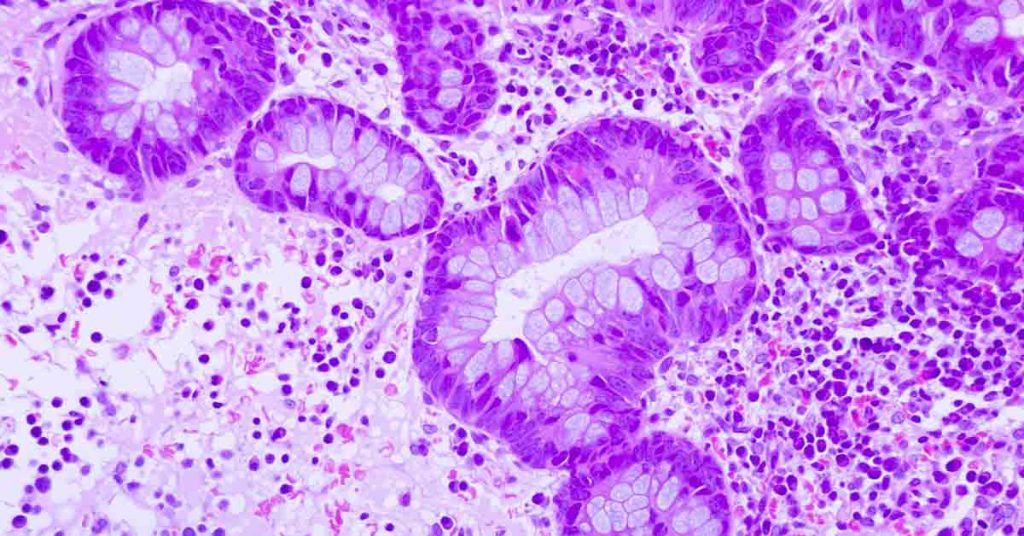

Bowel cancer refers to any cancer that develops in the large bowel, including the rectum and colon. Also known as colorectal cancer, the risk factors include family history, age, and existing medical conditions. A new study has additionally found that being overweight as a child and young adult increases your chances of subsequently developing bowel...